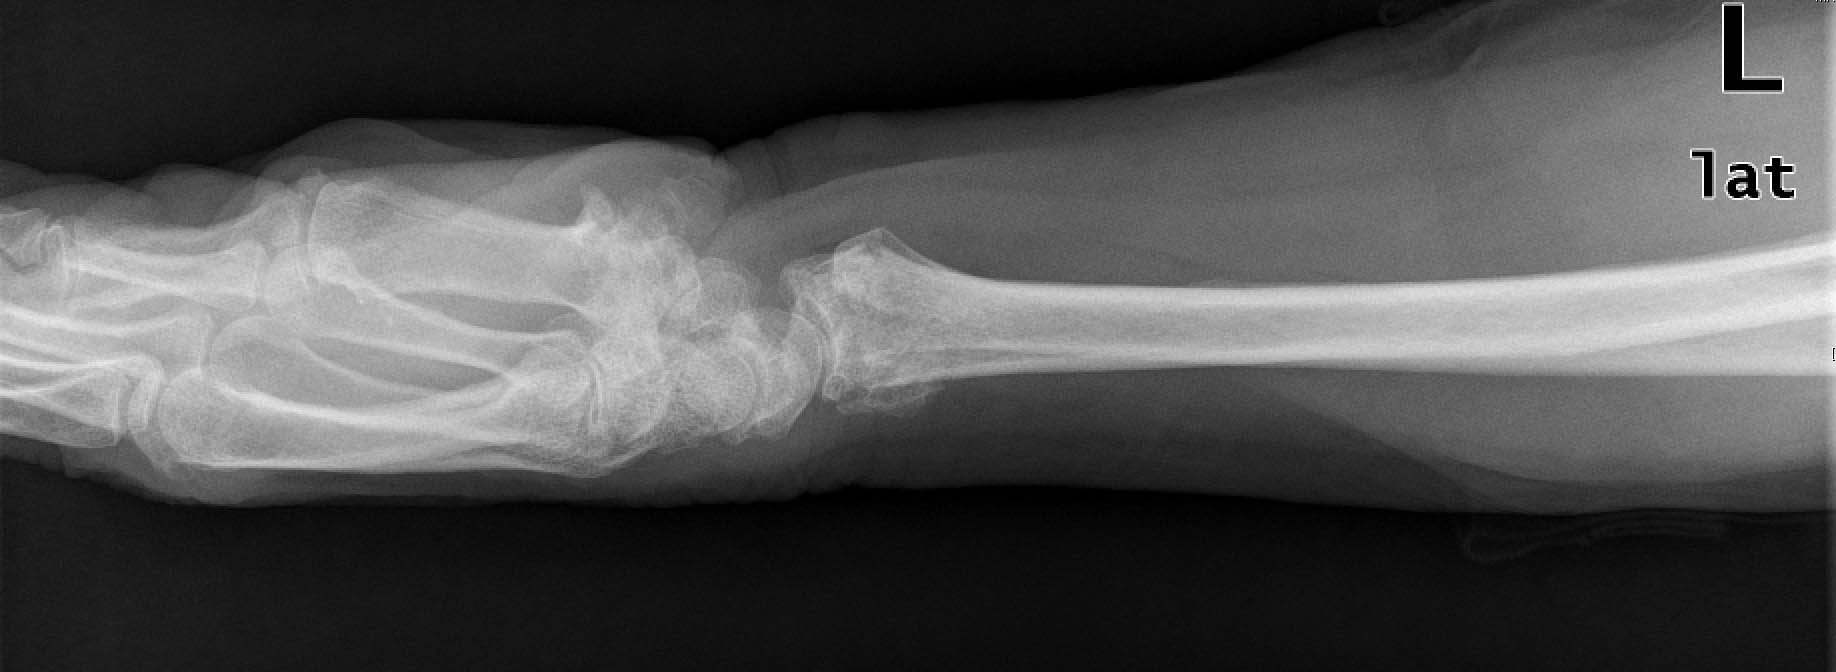

Deformidad de cúbito tras fracturas acumuladas

Deformidad de cúbito. fracturas acumuladas.